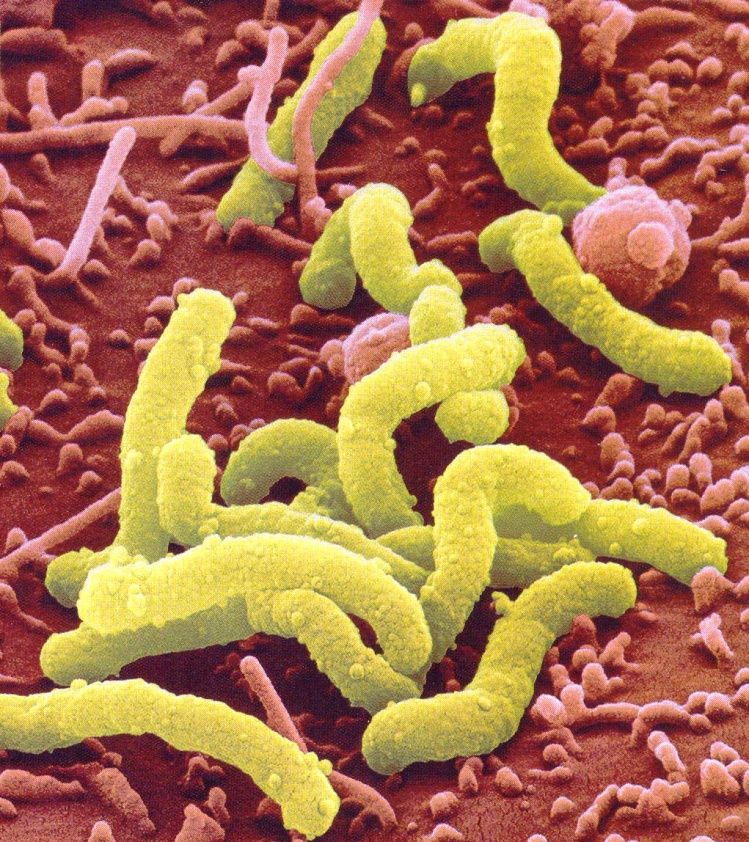

Кампилобактер фетус: патогенез и инфекции